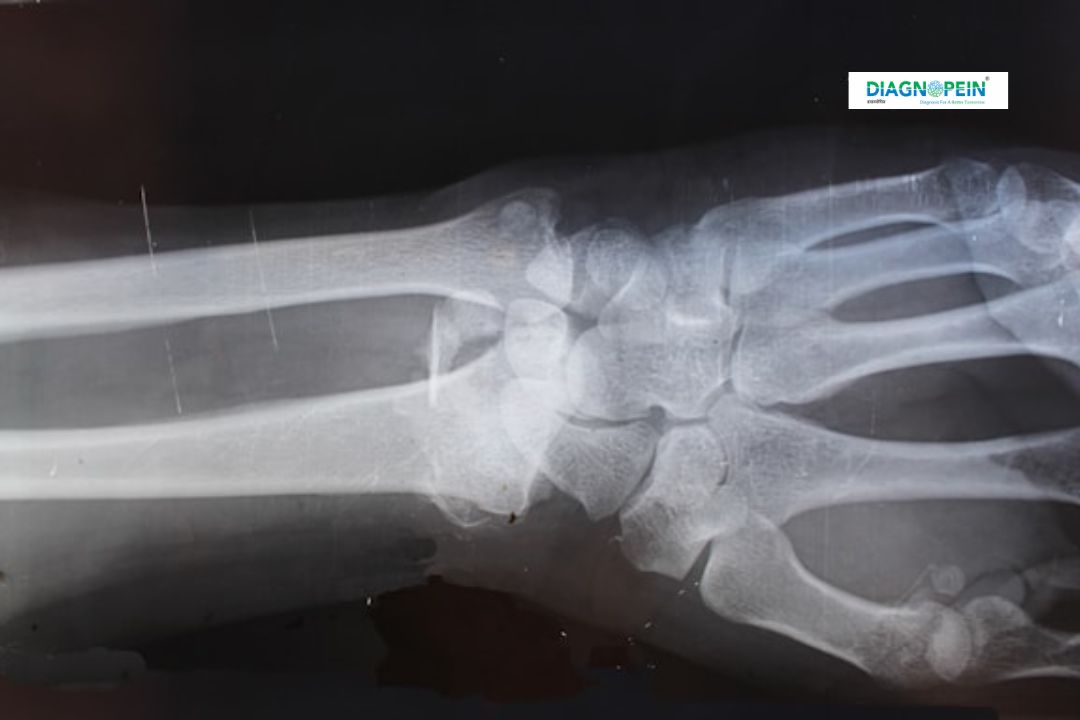

X-Ray Foot AP (Anteroposterior) View is a common diagnostic imaging technique used to evaluate the bones, joints, and alignment of the foot. At Diagnopein Diagnostic Center in Karad, we perform high-quality digital X-rays that help detect fractures, deformities, arthritis, infections, and other bone-related issues. This test produces a clear front-to-back image of the foot that allows doctors to assess injuries or abnormalities in detail.

The foot comprises several small bones, including tarsals, metatarsals, and phalanges. Even a minor injury can cause pain or affect motion. Getting an X-Ray Foot AP View in Karad at Diagnopein helps detect problems like:

Parameters Observed in X-Ray Foot AP View:

1. Bone density and alignment

2. Fracture lines or bone fragmentation

3. Joint space analysis

4. Soft tissue condition

5. Signs of arthritis or other bone diseases